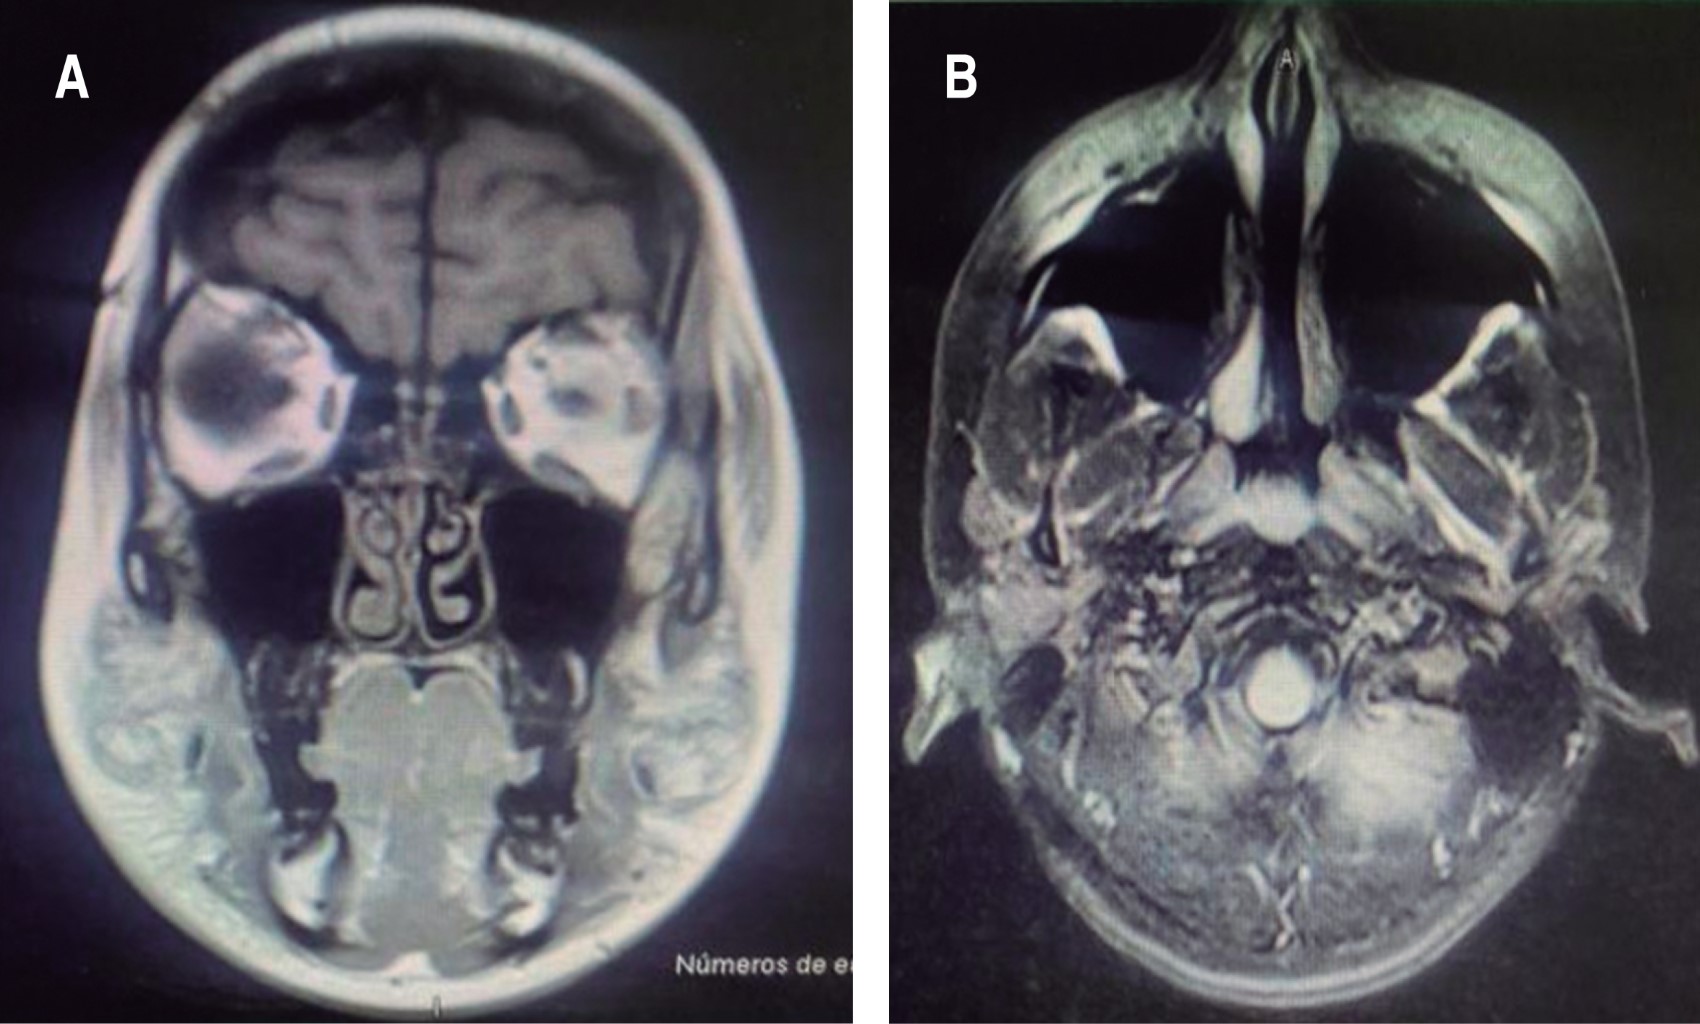

Cosmetic facial augmentation procedures using injections of different substances is common and has been increasing because it has come to be considered low risk, with good results and low cost; however, this is not always the case. Self-injection or injection of authorized or unauthorized materials or homemade formulas by personnel lacking anatomical knowledge and risks of the procedures has led to an increase in the incidence of multiple complications reported in the literature. Among the most common are deformities, granulomas, and infections, as well as the latent risk of skin necrosis. We present the case of a 15-year-old woman with a history of borderline personality, who reported having been psychologically abused at school because of the shape of her nose. She was admitted to hospital after having injected coconut oil and omega 3 with an insulin syringe in her nasal dorsum, nasal tip, lower lip and cheekbones. Given clinical data of regional inflammation, conservative management was started based on the literature and based on a multidisciplinary decision with corticosteroids and a double antibiotic scheme. Due to the satisfactory evolution of conservative and anti-inflammatory management, no surgical procedure was required. The symptoms were limited to 5 days, presenting gradual clinical improvement. We conclude that multidisciplinary management is essential in each patient, especially when there is psychological or psychiatric disorder.

Figure 1

Figure 2

Figure 3

Figure 4

Figure 5

Figure 6